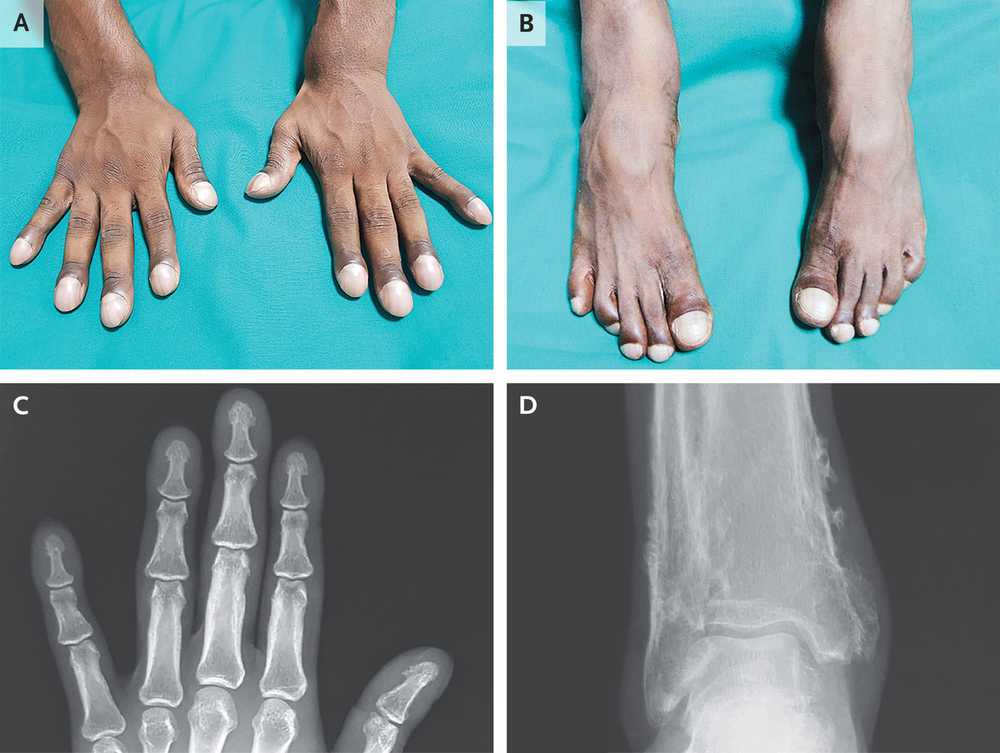

A 31-year-old man presented with 10 years of progressive fingertip and toe enlargement and intermittent aches of his distal forearms and lower legs.

Physical exam was notable for digital clubbing, proximal nail fold hyperpigmentation, and forearm and lower leg tenderness of palpation.

Plain radiographs of the ankles showed increased periosteal bone formation at the distal tibia and fibula. Serum laboratory tests, echocardiogram, and a whole-body PET-CT were normal.

What is the most likely diagnosis?